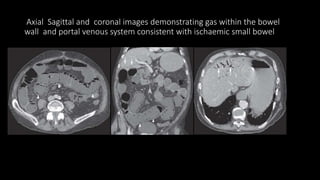

Axial Sagittal and coronal images demonstrating gas within the bowel

wall and portal venous system consistent with ischaemic small bowel

• In severe cases gas may be seen within the bowel wall appearing as

intramural locules of low attenuation.

• Gas may also be seen in the portal venous system as branching

peripheral low attenuation usually in the left lobe of the liver .